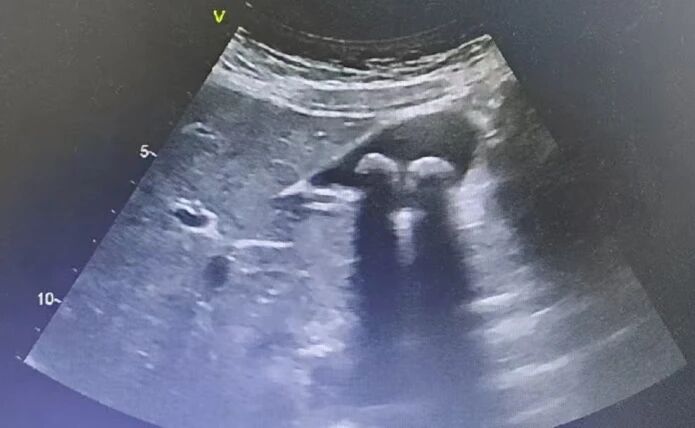

1.胆囊结石/胆囊炎:超声能清晰显示结石,并观察胆囊壁是否增厚、周围有无积液。

胆囊结石超声影像